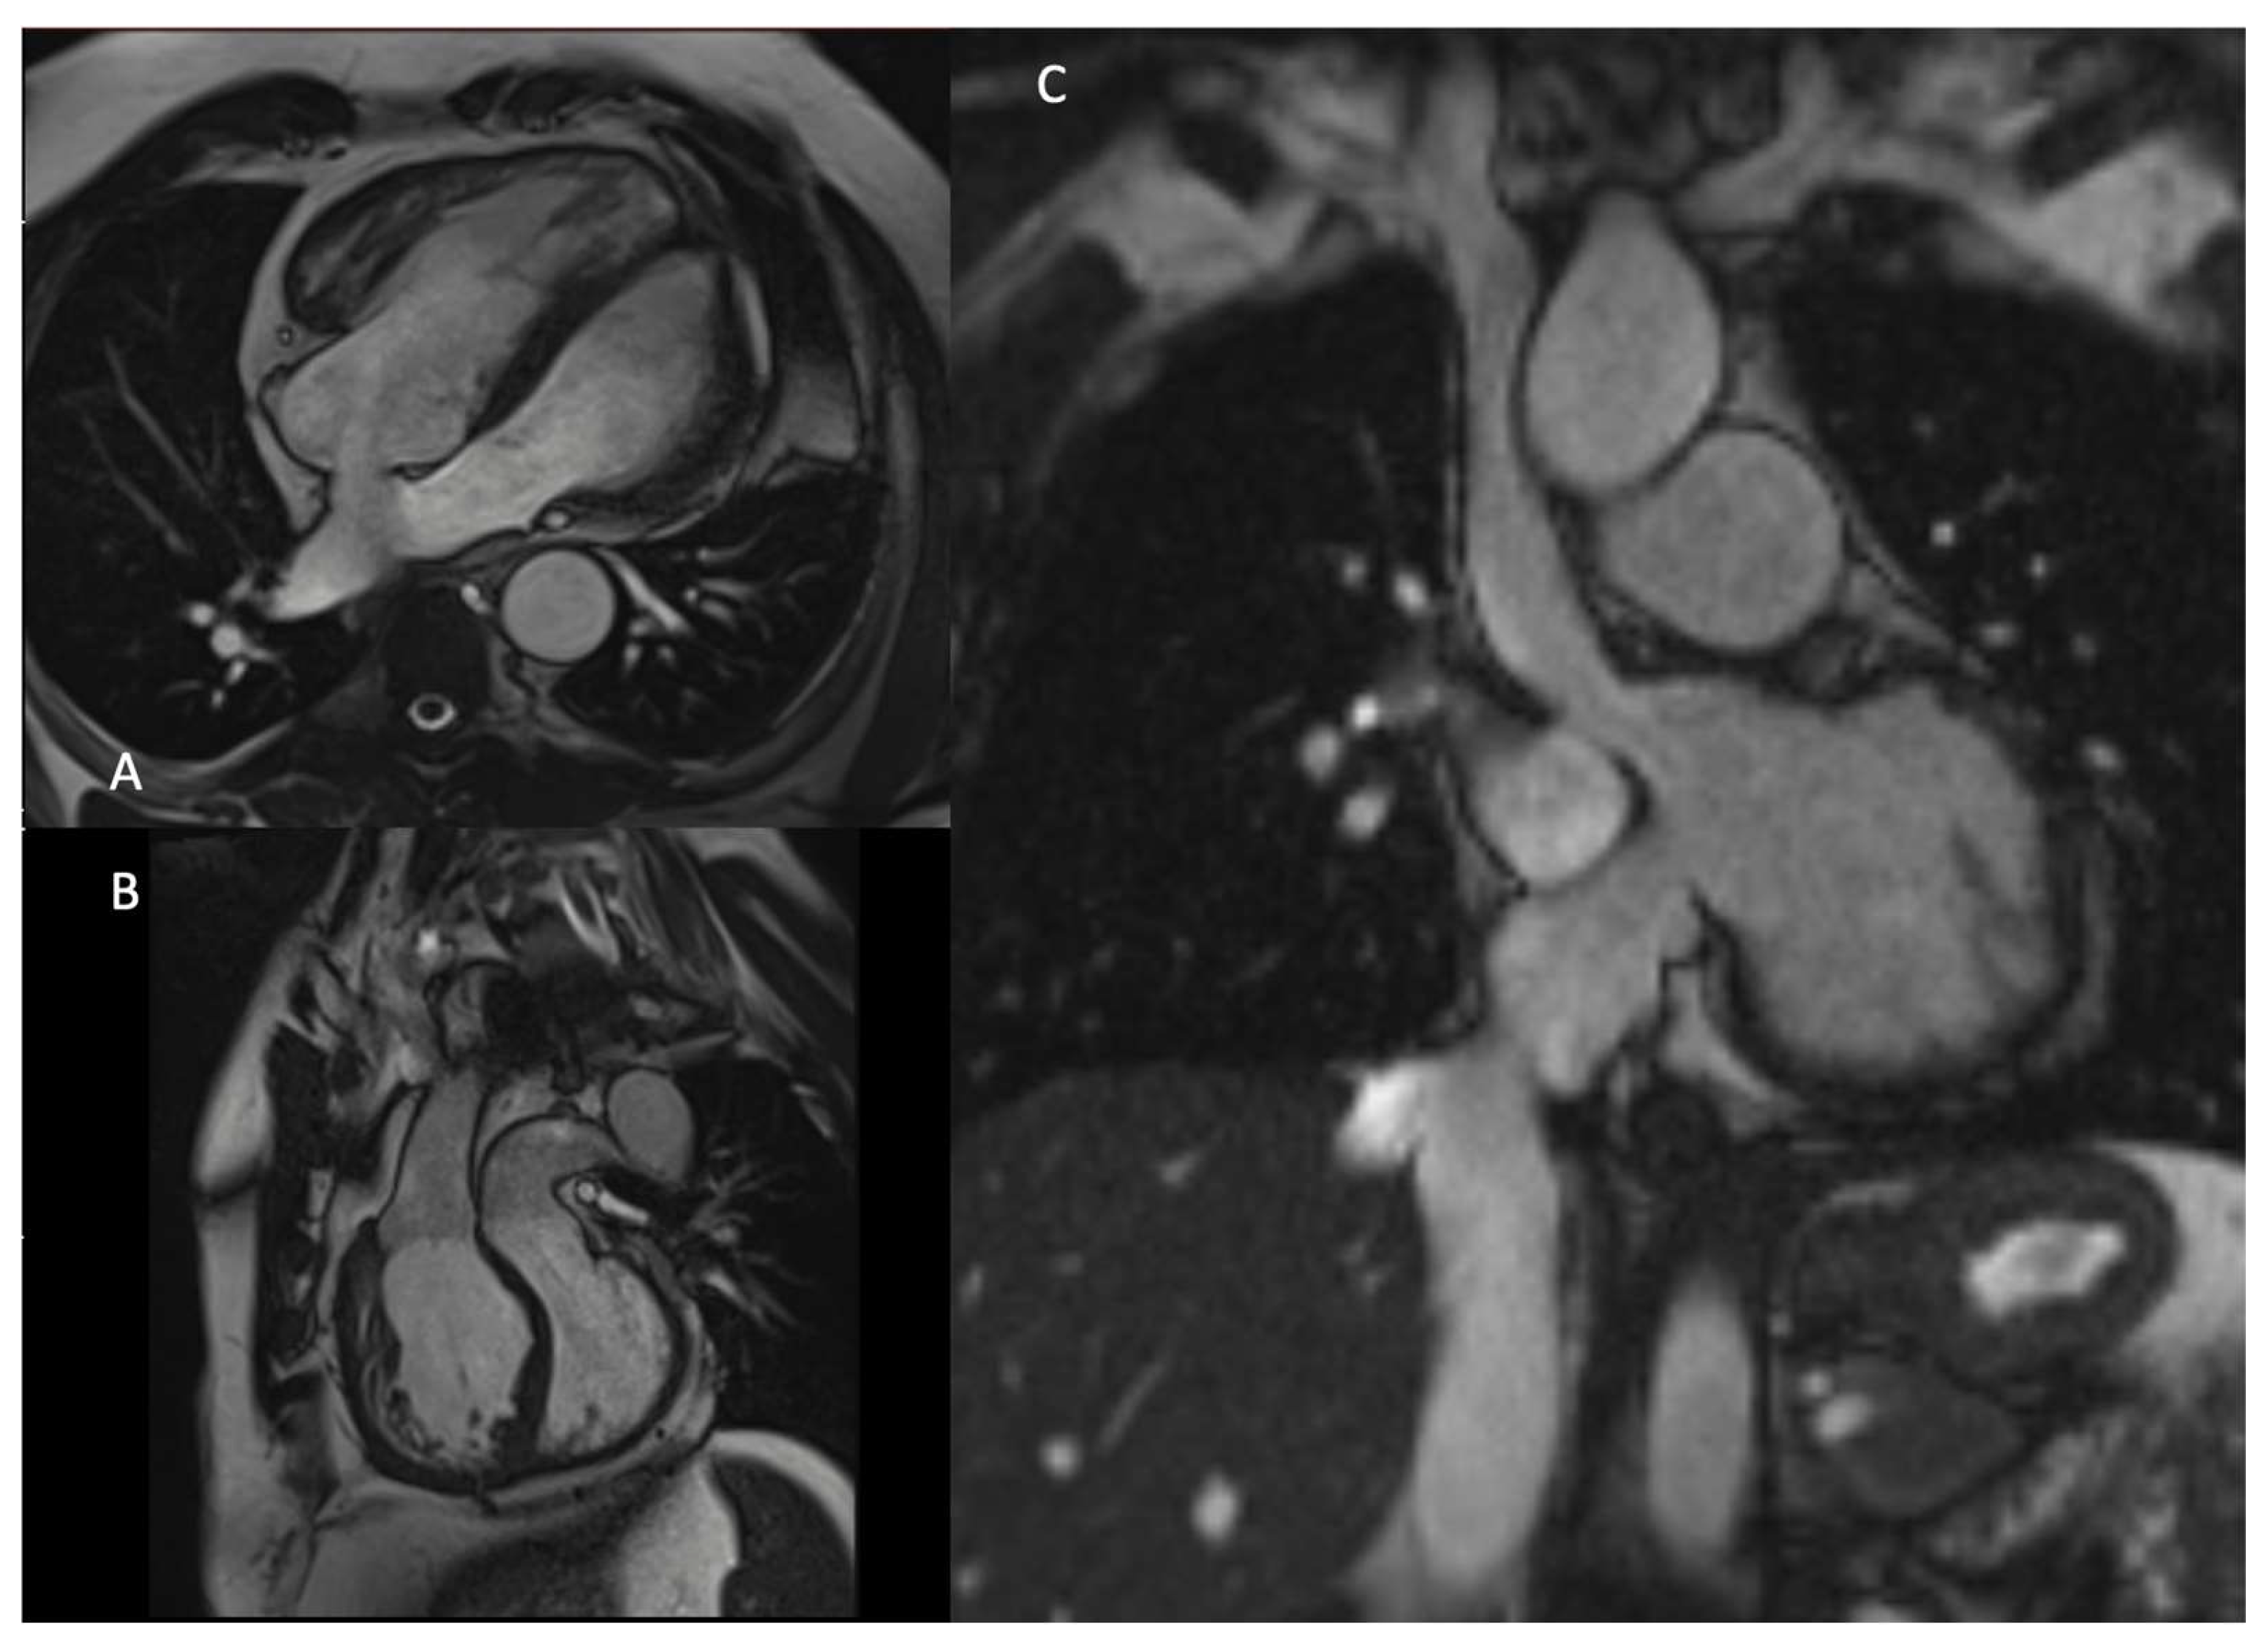

- Moscatelli, S.; Leo, I.; Lisignoli, V.; Boyle, S.; Bucciarelli-Ducci, C.; Secinaro, A.; Montanaro, C. Cardiovascular Magnetic Resonance from Fetal to Adult Life-Indications and Challenges: A State-of-the-Art Review. Children 2023, 10, 763. [Google Scholar] [CrossRef] [PubMed] [PubMed Central]

- Pozza, A.; Reffo, E.; Castaldi, B.; Cattapan, I.; Avesani, M.; Biffanti, R.; Cavaliere, A.; Cerutti, A.; Di Salvo, G. Utility of Fetal Cardiac Resonance Imaging in Prenatal Clinical Practice: Current State of the Art. Diagnostics 2023, 13, 3523. [Google Scholar] [CrossRef]

- Lloyd, D.F.A.; van Amerom, J.F.P.; Pushparajah, K.; Simpson, J.M.; Zidere, V.; Miller, O.; Sharland, G.; Allsop, J.; Fox, M.; Lohezic, M.; et al. An exploration of the potential utility of fetal cardiovascular MRI as an adjunct to fetal echocardiography. Prenat Diagn. 2016, 36, 916–925. [Google Scholar] [CrossRef] [PubMed] [PubMed Central]

- Porayette, P.; van Amerom, J.F.; Yoo, S.-J.; Jaeggi, E.; Macgowan, C.K.; Seed, M. MRI shows limited mixing between systemic and pulmonary circulations in foetal transposition of the great arteries: A potential cause of in utero pulmonary vascular disease. Cardiol. Young 2015, 25, 737–744. [Google Scholar] [CrossRef] [PubMed]

- Panayiotou, H.R.; Mills, L.K.; Broadbent, D.A.; Shelley, D.; Scheffczik, J.; Olaru, A.M.; Jin, N.; Greenwood, J.P.; Michael, H.; Plein, S.; et al. Comprehensive Neonatal Cardiac, Feed and Wrap, Non-contrast, Non-sedated, Free-breathing Compressed Sensing 4D Flow MRI Assessment. J. Magn. Reason. Imaging 2023, 57, 789–799. [Google Scholar] [CrossRef] [PubMed]